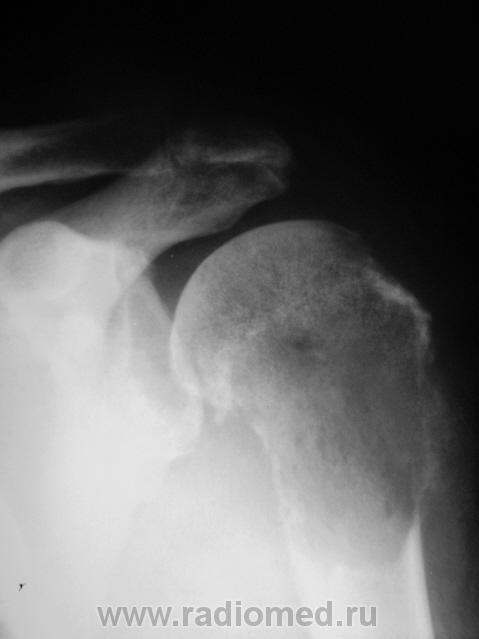

Нарушая все каноны обсуждения, но пользуясь тем, что Татьяна Валентиновна прокомментировала, хочу задать ей вопрос. Ваше мнение по поводу представленного ниже.

Хотела сразу написать "метастаз почечноклеточного рака". А если серьезно, Валентин Львович, подобная картина: литический очаг деструкции, со вздутием, разрушением коркового слоя, периостозом, требует морфологии, т.к. рентгеновская картина не специфична для какой-то определенной нозологии, диф. ряд включает и метастаз и первичную опухоль кости (прежде всего ходросаркома, остеосаркома, лимфома, ЗФГ).

Сам заключения не видел, но коллега терапевт информировал, что из областного ОД пришла гистология - "хондросаркома".